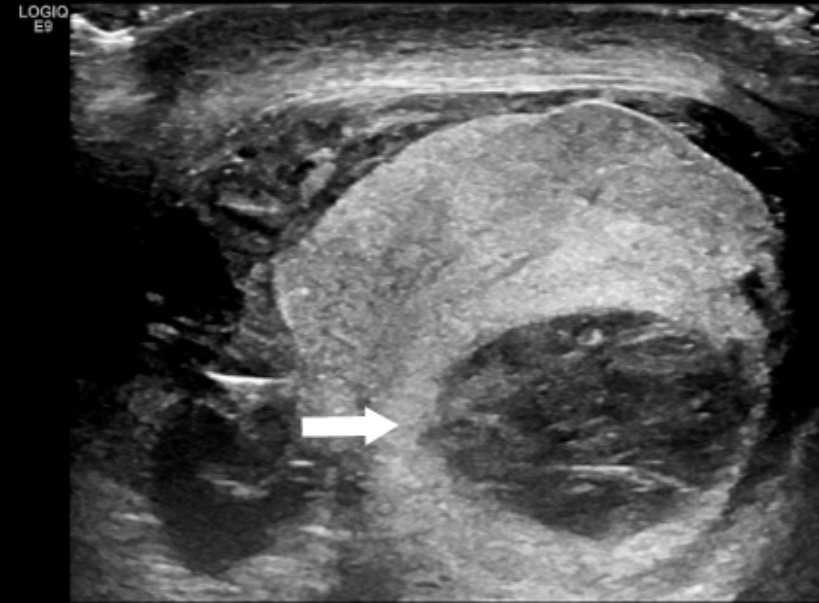

患者男,18岁,患者诉1小时前坐电动车不慎与汽车发生碰撞,电动车摔倒,摔伤会阴部,随即出现会阴疼痛,并逐渐肿胀,向下腹部放射,无尿频、尿急、尿痛,无恶心、呕吐,无心慌胸闷,无发热,院外未处理,为求进一步治疗来诊。专科检查:右侧阴囊肿大,局部可见淤血并触痛,查体不能完全配合,右侧睾丸及附睾形态不能触及明确轮廓。彩超所见:右侧睾丸体积增大,大小约5.7 * 2.6 * 4.1 cm,内回声不均匀,内可见小片状低弱回声,内可见点条状血流信号,右侧附睾头部形态尚可,尾部结构杂乱,血流信号略多,周围可见少量片状液性暗区,内透声欠佳。右侧阴囊内探及片状低回声,宽约0.6 cm。左侧睾丸及附睾大小形态可,实质回声未见明显异常,双侧精索未见增粗。超声提示:右侧睾丸、附睾外伤后,阴囊内少量积血。1日后患者查体见阴囊血肿较昨日增大,张力增高,遂复查超声,彩超所见:右侧睾丸增大,形态不规则,睾丸包膜不连续(图1),实质内回声不均匀,可见多个大小不等的偏低回声区,边界清,内回声不均匀,测大者约4.4 * 1.9 * 1.6 cm,CDFI示:右侧睾丸实质回声均匀区血流略丰富。右侧附睾显示不清。同侧睾丸鞘膜腔内可见不均质回声区,较宽处约1.3 cm。同侧精索未见增粗。超声提示:右侧睾丸破裂、多发血肿,右侧睾丸鞘膜腔血肿。术前诊断:1. 右侧睾丸挫伤,2. 阴囊血肿。于2025年6月19日行“右侧睾丸探查术”。手术记录:取右侧阴囊前外侧纵切口长约6 cm,依次切开皮肤、阴囊肉膜,显露并游离右侧鞘膜囊,打开鞘膜囊壁层,见大量血凝块约100 ml,应用吸引器吸净淤血,探查见右侧睾丸破裂,为横断伤,自睾丸中下四分之一分界位置横行撕裂至睾丸附睾连接部,睾丸血供差,附睾连续性存在,吸出睾丸内血凝块,切除坏死睾丸组织,切修睾丸创缘见切缘有鲜血渗出,应用1号丝线间断缝合睾丸白膜,缝合完毕后再次检查睾丸张力不高,应用温热生理盐水纱布覆盖于睾丸约10分钟,见剩余睾丸颜色有好转,由暗黑色逐渐变成淡红色,决定保留剩余睾丸,仔细止血。检查术野无出血,清点器械纱布无误后,于右侧阴囊底部戳孔放置引流管一根,固定于阴囊皮肤上。患者住院1月后出院。术后2月复查,彩超所见:右侧睾丸增大,形态不规则,睾丸包膜不连续,实质内回声不均匀,可见多个条索状偏低回声区,CDFI示:右侧睾丸实质内血流信号可。右侧附睾略大,血流信号略丰富,同侧精索未见增粗。超声提示:右侧睾丸外伤治疗后声像图。

Figure 1. Discontinuity of the tunica albuginea

1. 睾丸白膜连续性中断

睾丸损伤声像图通常分4型[3]:(1) 挫伤型:患侧睾丸增大,内部回声强弱不均,但包膜完整,形态无异常,睾丸周围仅可见无回声区;(2) 血肿型:患侧睾丸明显增大,但仍显示典型的卵圆形态,其实质回声不均,损伤区周围可由无回声晕围绕,有时可显示完全的无回声区;(3) 部分裂伤型:患侧睾丸增大,内部回声不均匀,可有无回声区,裂口处的包膜线样回声突然中断,睾丸失去卵圆形形态,裂口周围或下方可见不规则高回声区和无回声区;(4) 严重裂伤及破裂型:严重裂伤时裂口距离可达2.5 cm以上,沿裂口周围有大片液性无回声区或不规则高回声区,破裂时患侧睾丸增大,形态严重失常,正常睾丸回声显示不清,其周围有大量液性无回声区。超声检查对于明确睾丸的完整性和血运具有重要意义:(1) 可以准确判断单纯阴囊血肿和睾丸破裂;(2) 根据睾丸白膜的完整性和有无睾丸组织突出白膜外可以鉴别睾丸破裂和睾丸挫伤,以及睾丸内血肿的存在,进而确定手术治疗是否必要。早期超声诊断对睾丸破裂诊断准确率可达95% [1]。对诊断睾丸破裂有提示意义的超声图像包括:睾丸轮廓回声中断(睾丸白膜破裂),睾丸实质内单个或多个不规则且边界欠清的低回声区(睾丸实质血肿) (图2)。在条件允许时,阴囊受伤后应尽快接受超声检查,即使仅有单纯阴囊血肿或睾丸实质小血肿,在超声检查监视下进行保守治疗也更为安全。近年来高分辨力超声诊断和彩色多普勒超声技术的应用,进一步提高了对阴囊损伤特别是睾丸血流状态判断的准确性,对睾丸扭转的诊断具有重要价值。此外,超声诊断对易疏忽的双侧睾丸损伤的诊断具有特殊意义。本例患者首次超声检查受较大阴囊血肿遮挡及设备增益调节范围不全面的影响未能及时发现睾丸包膜不连续,后因阴囊血肿较前日增大,张力增高,复查超声发现了睾丸破裂,结合患者病史及临床表现也在术前明确了诊断。